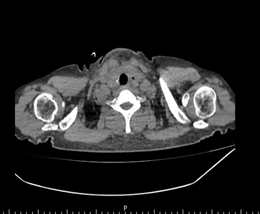

术前检查发现,余女士甲状腺右叶结节达到 10*7*5 厘米大小,气管明显受压移位。因患有慢性肾功能衰竭、肥厚型心肌病、高血压病 3 级,2 型糖尿病等多种内科疾病,长期血液透析治疗,余女士及家属对手术治疗有一定的顾虑。